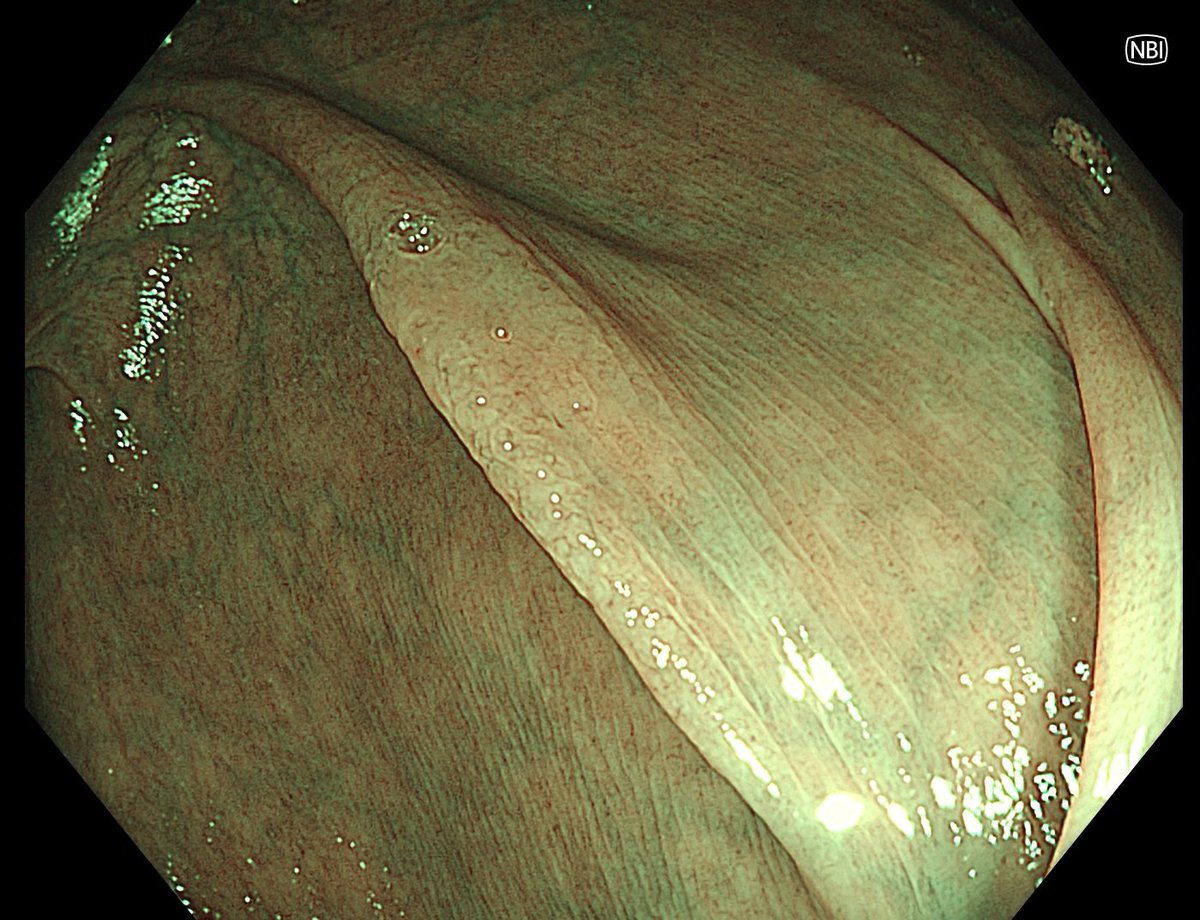

1. Antrum, low grade dysplasia. Removed via ESD. Specimen 43x32mm / dysplasia 20x13mm. R0